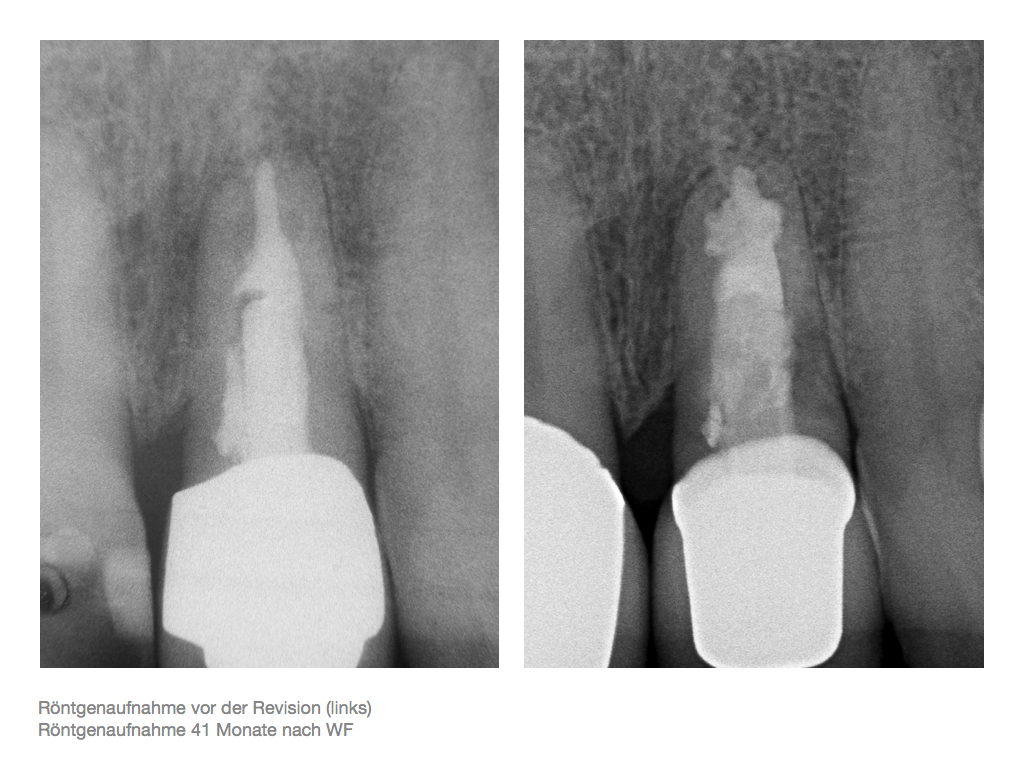

IF.076 Veröffentlicht 3. November 2012 am 1024 × 768 in Zahnerhalt „austherapierter“ Zähne durch endochirurgische Maßnahmen